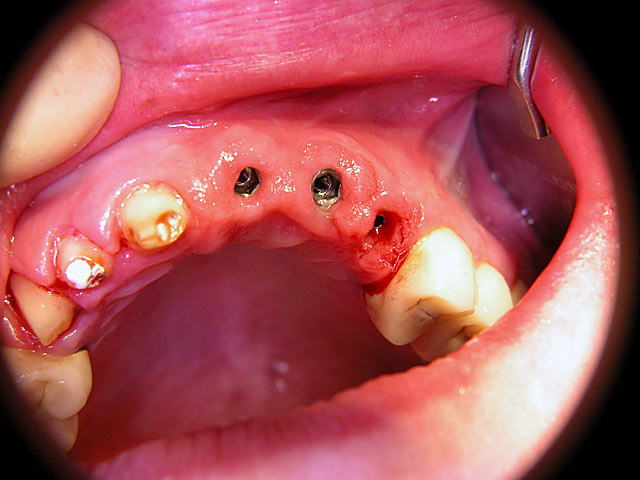

Die folgenden Patientenfälle sollen Ihnen einen Einblick in die Möglichkeiten der modernen Implantation geben.

Kugelkopf-Implantation: